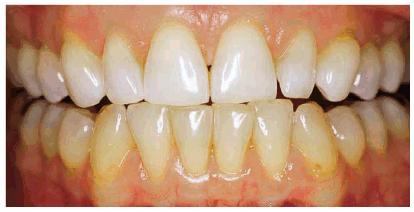

Figure 16-1A: An otherwise attractive smile is marred by discolored teeth.

Figure 16-1B: After tooth lightening, the smile is much more pleasing.